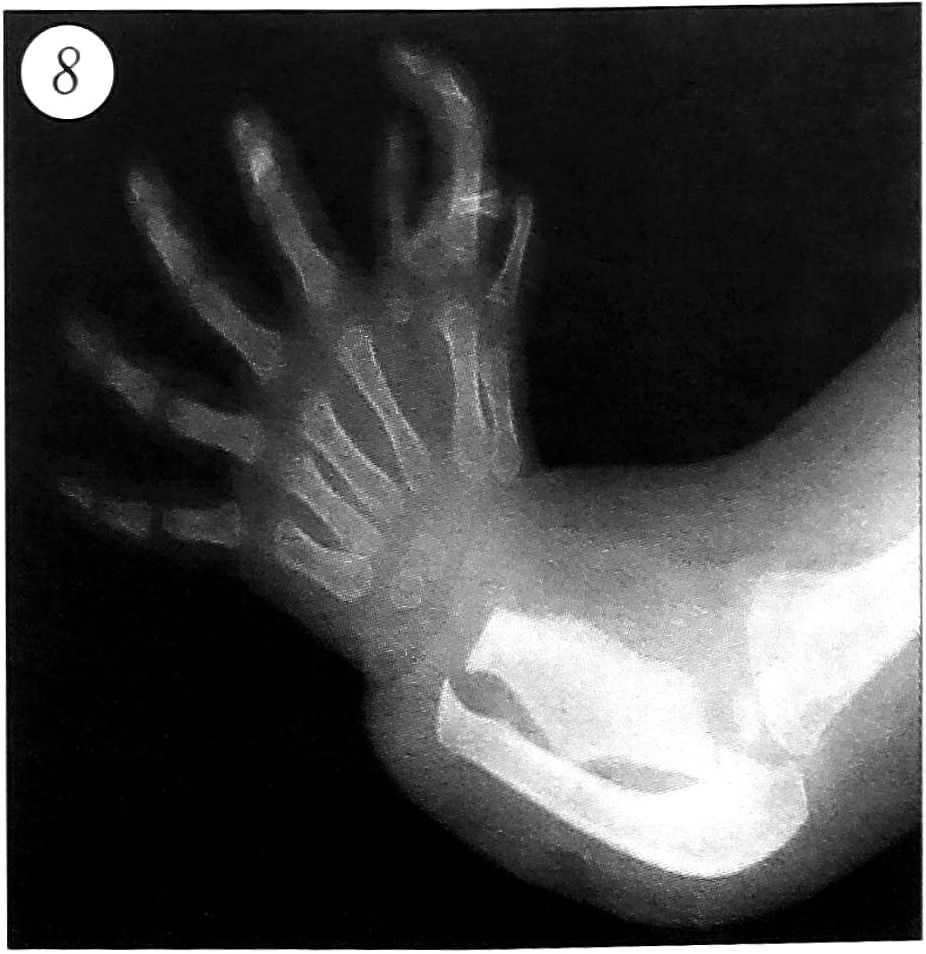

- Сочетание трехфалангизма с радиальной полидактилией. Нами выделено два варианта сочетания трехфалангизма с радиальной полидактилией: 1) с изолированным поражением кисти; 2) с поражением предплечья и кисти.

В 1-й группе выявлены следующие разновидности (рис. 7): трехфалангизм в сочетании с радиальной полифалангией; трехфалангизм в сочетании с неполным (полным) удвоением (утроением) I луча; трехфалангизм в сочетании с радиальной и центральной полидактилией (вариант «зеркальной кисти»). 2-я группа была представлена трехфалангизмом I пальца кисти в сочетании с радиальной и центральной полидактилией, а также аномалией развития костей предплечья (вариант «зеркальной кисти») (рис. 8).

Рис. 8. Трехфалангизм I пальца кисти в сочетании с радиальной и центральной полидактилией, а также аномалией развития костей предплечья.

Брахимезофалангеальные и долихофалангеальные формы трехфалангизма основного и дополнительного лучей с характерными признаками, описанными выше, в 1-й группе больных встречались с примерно одинаковой частотой, нередко отмечалась гипоплазия дополнительных I лучей. Во 2-й группе наблюдались лишь долихофалангеальные формы.